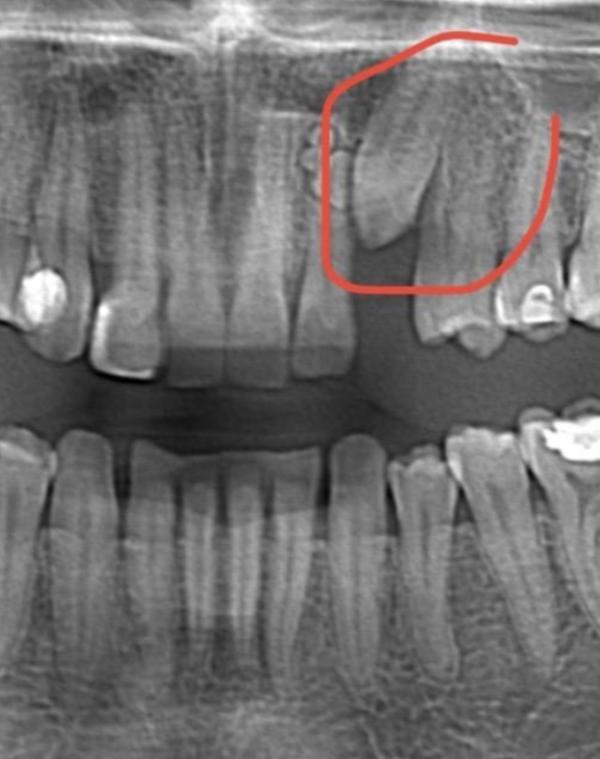

У нас вообщем не возит 1 резец с права.

Сходили на снимок зубов ребенку. И там вообщем зубик растает криво, есть вероятность что не выйдет.

Прикрепляю примерные фото😅 снимок забыла сфотать